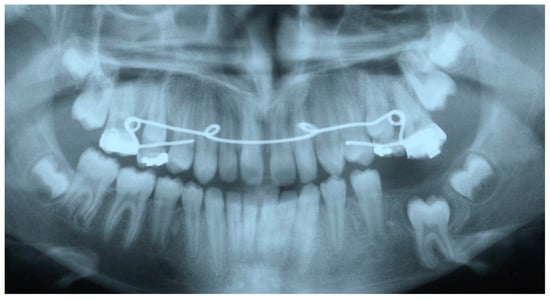

2. Case Presentation